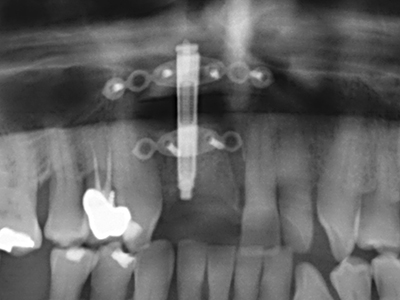

Aplicación: Preparación cerca del nervio

Como ya se ha mencionado, en el ámbito de la odontología conservadora también existen áreas en las que está indicada la cirugía piezoeléctrica. El uso de insertos de trabajo especiales facilita la representación del ápice radicular y, sobre todo en el área de los premolares inferiores y superiores, protege mejor los nervios y las mucosas del seno maxilar. En el caso de un cierre apical no estanco, los insertos de diamante acodados preparan de forma exacta y selectiva la cavidad de resección para el material de relleno retrógrado de la raíz. Gracias a la técnica de ultrasonidos, los insertos pueden presentar un diseño muy estilizado, lo que mejora la visión global y el tamaño de la cavidad de acceso. De este modo, en esta indicación, el uso de la cirugía por ultrasonidos se encuentra entre los métodos estándar para una apicectomía (Del Fabbro, Tsesis et al. 2010, Scarano, Artese et al. 2012).

Aplicación: Apicectomía

Si es preciso realizar intervenciones quirúrgicas en las que el hueso está en contacto directo con estructuras sensibles, como son los vasos sanguíneos o los nervios, los instrumentos rotativos presentan un enorme potencial de provocar lesiones iatrogénicas. Así, precisamente en la representación de nervios después de una lesión iatrogénica, o en el transcurso de la lateralización de un nervio para resecciones, reconstrucciones o incorporación de implantes, los equipos piezoeléctricos pueden resultar muy útiles para preparar la tapa ósea y retirar las partes de tejido duro cercanas al nervio (fig. 17-20). Por lo general, un ligero contacto del cordón nervioso con el inserto piezoeléctrico no tiene consecuencia alguna; ahora bien, un procedimiento poco cuidadoso con movimientos tipo sierra o piezas de trabajo sobre la base ósea aún existente puede provocar lesiones nerviosas temporales o incluso permanentes. Con todo, el riesgo de sufrir una lesión de este tipo se considera significativamente inferior que en los casos en los que se utilizan sierras y fresas (Pereira, Gealh et al. 2014).